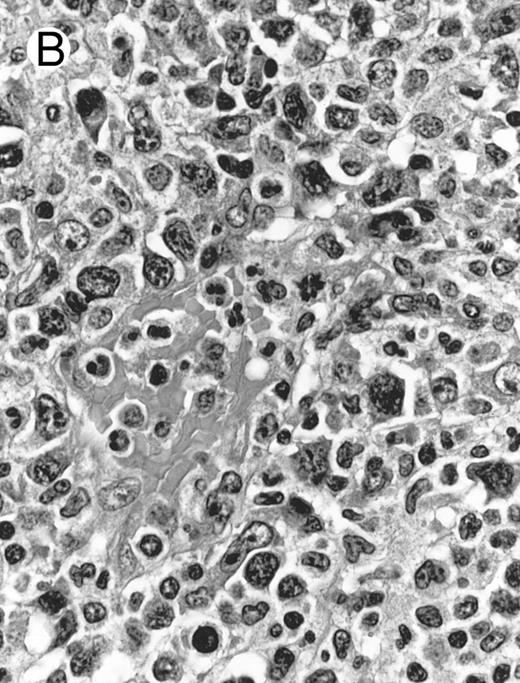

Lymph node biopsy of aggressive NK cell leukemia/lymphoma (case no. 37). There is a fairly monotonous, diffuse infiltrate of medium-sized cells with round nuclei. The neoplastic cells in this case resemble plasmacytoid monocytes.

There were very few to numerous granular lymphocytes in the peripheral blood. Some of the granular lymphocytes were indistinguishable from normal large granular lymphocytes, with round nuclei, dense chromatin, and pale cytoplasm with fine azurophilic granules (Fig 5A). Some granular lymphocytes had larger nuclei with more open chromatin and distinct nucleoli (Fig 5B); occasional nuclei could show indentations. The azurophilic granules were sometimes large and coarse. There were also circulating normoblasts and immature myeloid cells. Marrow involvement ranged from subtle to extensive. In histologic sections, irrespective of site, there was a monotonous infiltrate of medium-sized cells with round nuclei and fairly condensed chromatin (Fig 6). Karyorrhexis was prominent. The infiltrate was diffuse, interstitial, or angiocentric.